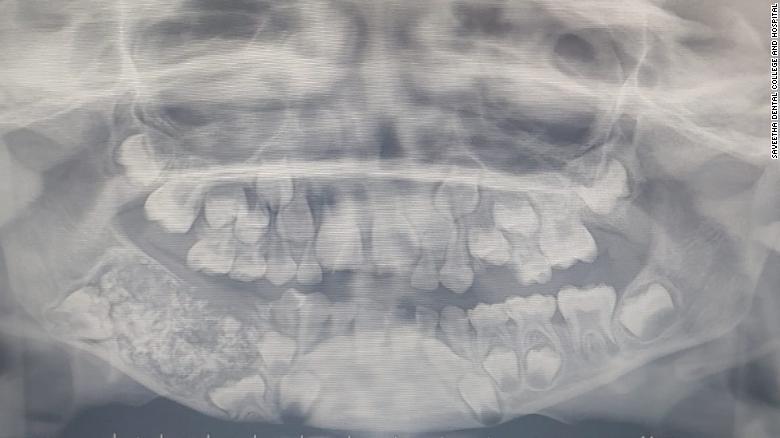

După ce i-au făcut radiografie, specialiștii au constatat că baiatul avea nici mai mult, nici mai puțin de 526 de dinți. Copilul avea o pungă în falca joasă plină cu dinți anormali.

Doi medici s-au ocupat de operarea copilului pentru a-i îndepărta punga în care au găsit sute de dinți.